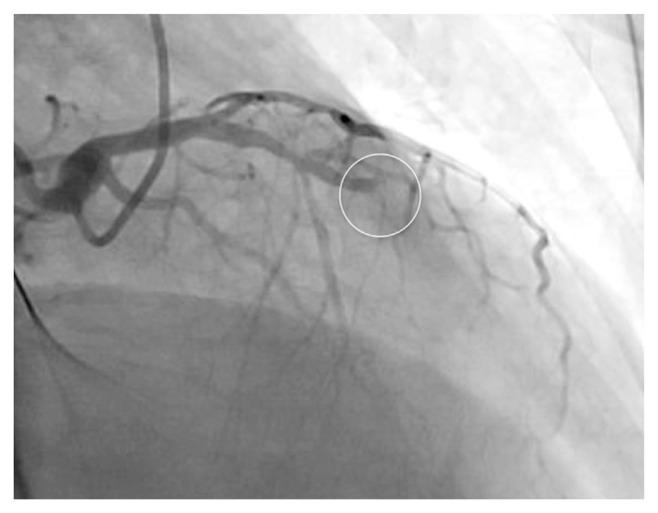

Stent loss during percutaneous coronary intervention (PCI) is uncommon but may lead to serious adverse events. Here we describe a challenging case of stent loss in the radial artery during primary PCI. There, a long stent failed to cross the culprit lesion, and an attempt to pull back the undeployed stent into the guiding catheter resulted in eversion of the stent, partially stripping it off the stent balloon and rendering the stent irretrievable. Retrieval of the stent at all costs might have led to major complications; hence stent deployment in the radial artery bailed us out of this precarious situation.

经皮冠状动脉介入治疗(PCI)期间支架丢失并不常见,但可能导致严重不良事件。在此,我们描述一例在初次PCI期间桡动脉发生支架丢失的具有挑战性的病例。在该病例中,一个长支架未能通过罪犯病变,试图将未展开的支架拉回到引导导管时导致支架翻转,部分从支架球囊上剥离,使支架无法取回。不惜一切代价取回支架可能会导致严重并发症;因此,在桡动脉中部署支架使我们摆脱了这种危险的情况。